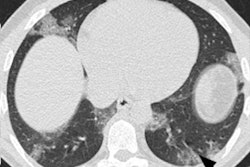

DetectedX was established to aid doctors and radiologists diagnose breast cancer, lung cancer, and COVID-19 faster and more accurately. Its online on-demand educational platform aims to improve radiological detection and is used by more than 3,000 users across 150 countries.